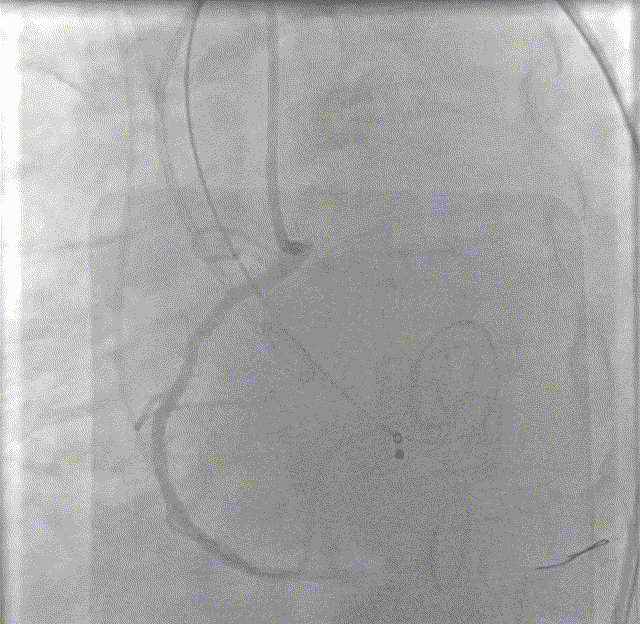

主动脉根部造影

术后造影

入路造影